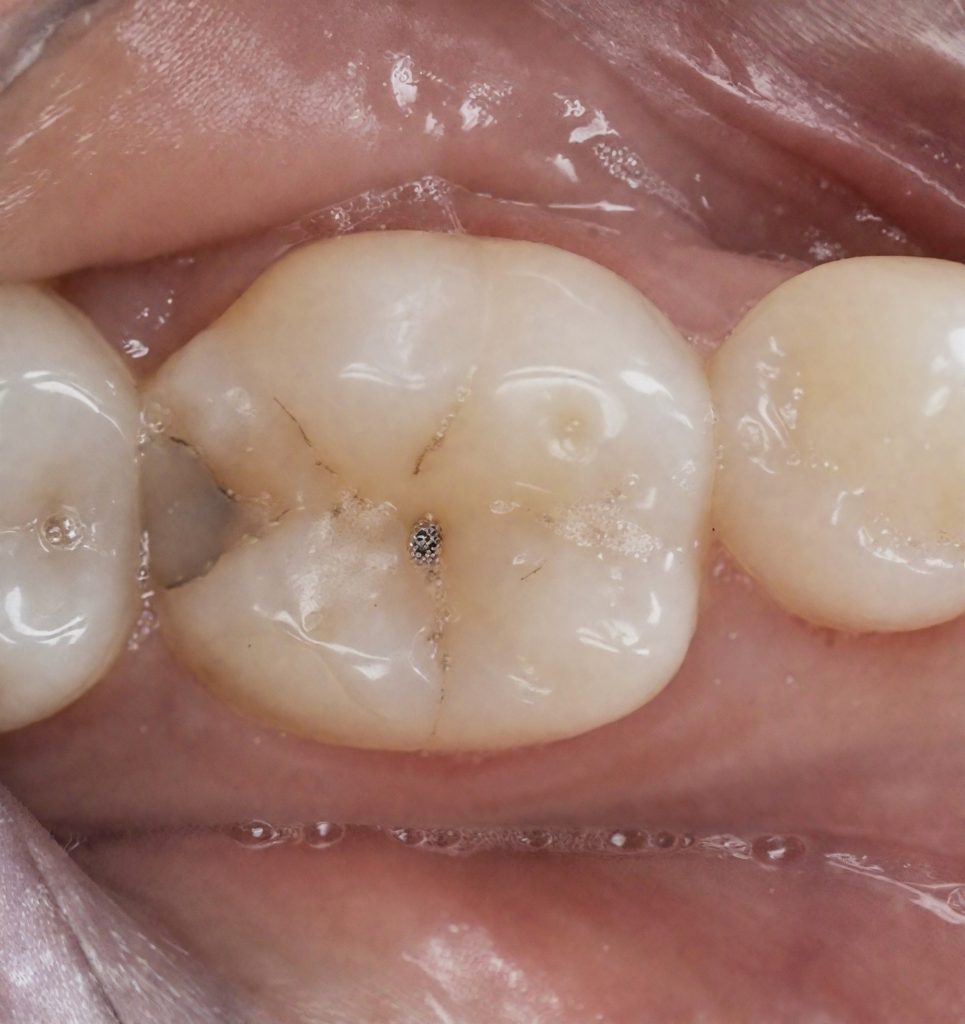

1. CASE OVERVIEW

The patient presented with food impaction and discomfort around the distal surface of the mandibular first molar. Clinical inspection showed a defective contact and marginal staining. Radiographic evaluation confirmed a proximal carious lesion with no pulpal involvement. The objective was simple:

restore the tooth conservatively, rebuild a natural contact, and protect the periodontal space.

4.2 Caries Removal

The old stained fissures and proximal lesion were accessed minimally.

Dark, demineralized dentin was removed carefully with controlled speed burs. The deepest dentin was preserved following selective caries removal to avoid unnecessary pulp stress.

You can clearly see in the photos:

- clean peripheral enamel

- sound dentin base

- a defined proximal box ready for matrix placement